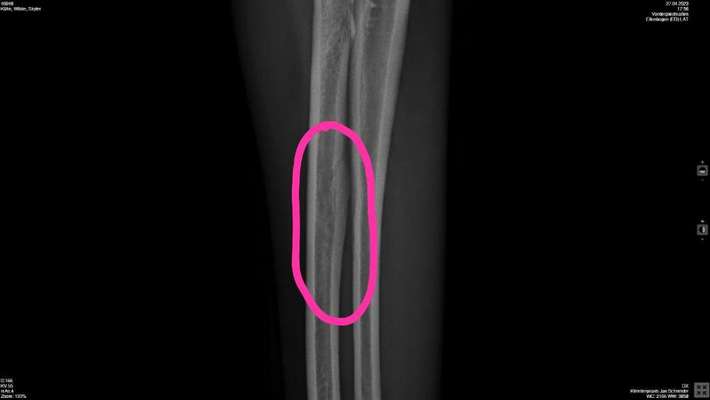

Seit Samstag humpelt Skyler immer mal wieder. Am Montag waren wir beim Tierarzt. Es wurde erstmal nichts gravierendes festgestellt. Sie bekam dann erstmal ein Schmerzmittel und wir sollen weiter beobachten. Leider trat bisher keine Besserung ein. Vor allem nach längerem Liegen wird es eher schlimmer. Gestern sind wir dann nochmal zum Tierarzt. Dort wurden die Vorderbeine geröntgt. Sie hat an beiden Vorderbeinen Veränderungen am Knochen. Was genau das nun ist wissen wir bisher nicht. Müssen jetzt noch zu einem Spezialisten. Leider haben wir erst am 9.5. einen Termin bekommen. Ich bin im Moment ziemlich traurig. Die Maus ist noch nicht mal drei Jahre alt und dann schon sowas. Habt ihr noch Ideen wie ich der Maus bis dahin das Leben erleichtern kann?

Heute waren wir bei einem Orthopäden/Chirurg für Hunde. Erstmal ist im Moment in nicht deutlich feststellbar ob Skyler noch Schmerzen hätten da sie ja unter Schmerzmitteln steht. Das Röntgenbild ist wohl nicht schlimm. Das was so aufgeschwemmt aussiehst ist die Stelle, wo die Sehne mit dem Knochen verbunden ist. Es ist bei Skyler deutlich ausgeprägter als normal. Nur bei der Untersuchung war die linke Schulter etwas in der Bewegung eingeschränkt. Wir setzen jetzt erstmal die Schmerzmittel ab, um rauszufinden, ob die Schmerzen tatsächlich weg sind oder ob sie nur "unterdrückt" sind. Wenn kein humpeln mehr kommt, alles gut, wenn das humpeln wieder los geht, haben wir nächsten Dienstag einen Termin, an dem dann in Sedierung die Schulter genauer betrachtet wird. Also weiter Daumen drücken.